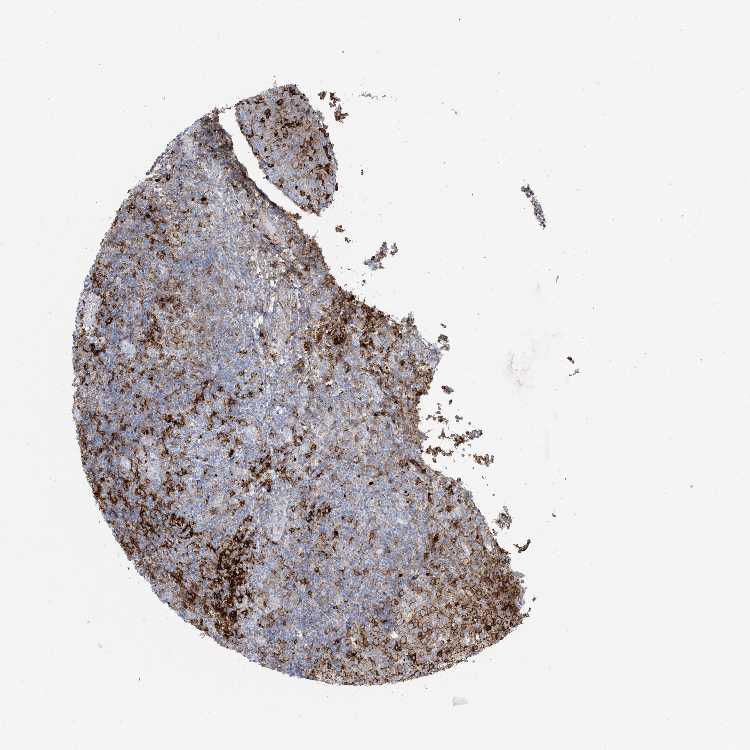

Tonsil

TONSIL - Expression summary

TONSIL - Antibody stainingi

Antibody staining in the annotated cell types in the current human tissue is reported as not detected, low, medium, or high, based on conventional immunohistochemistry profiling in selected tissues. This score is based on the combination of the staining intensity and fraction of stained cells.

Each image is clickable and will lead to virtual microscopy that enables deeper exploration of all samples and also displays staining intensity scores, fraction scores and subcellular localization as well as patient and tissue information for each sample.

Antibody HPA043151Antibody CAB015400Antibody CAB034021

Germinal center cells MediumHighHigh

Non-germinal center cells MediumMediumHigh

Squamous epithelial cells Not detectedNot detectedNot detected